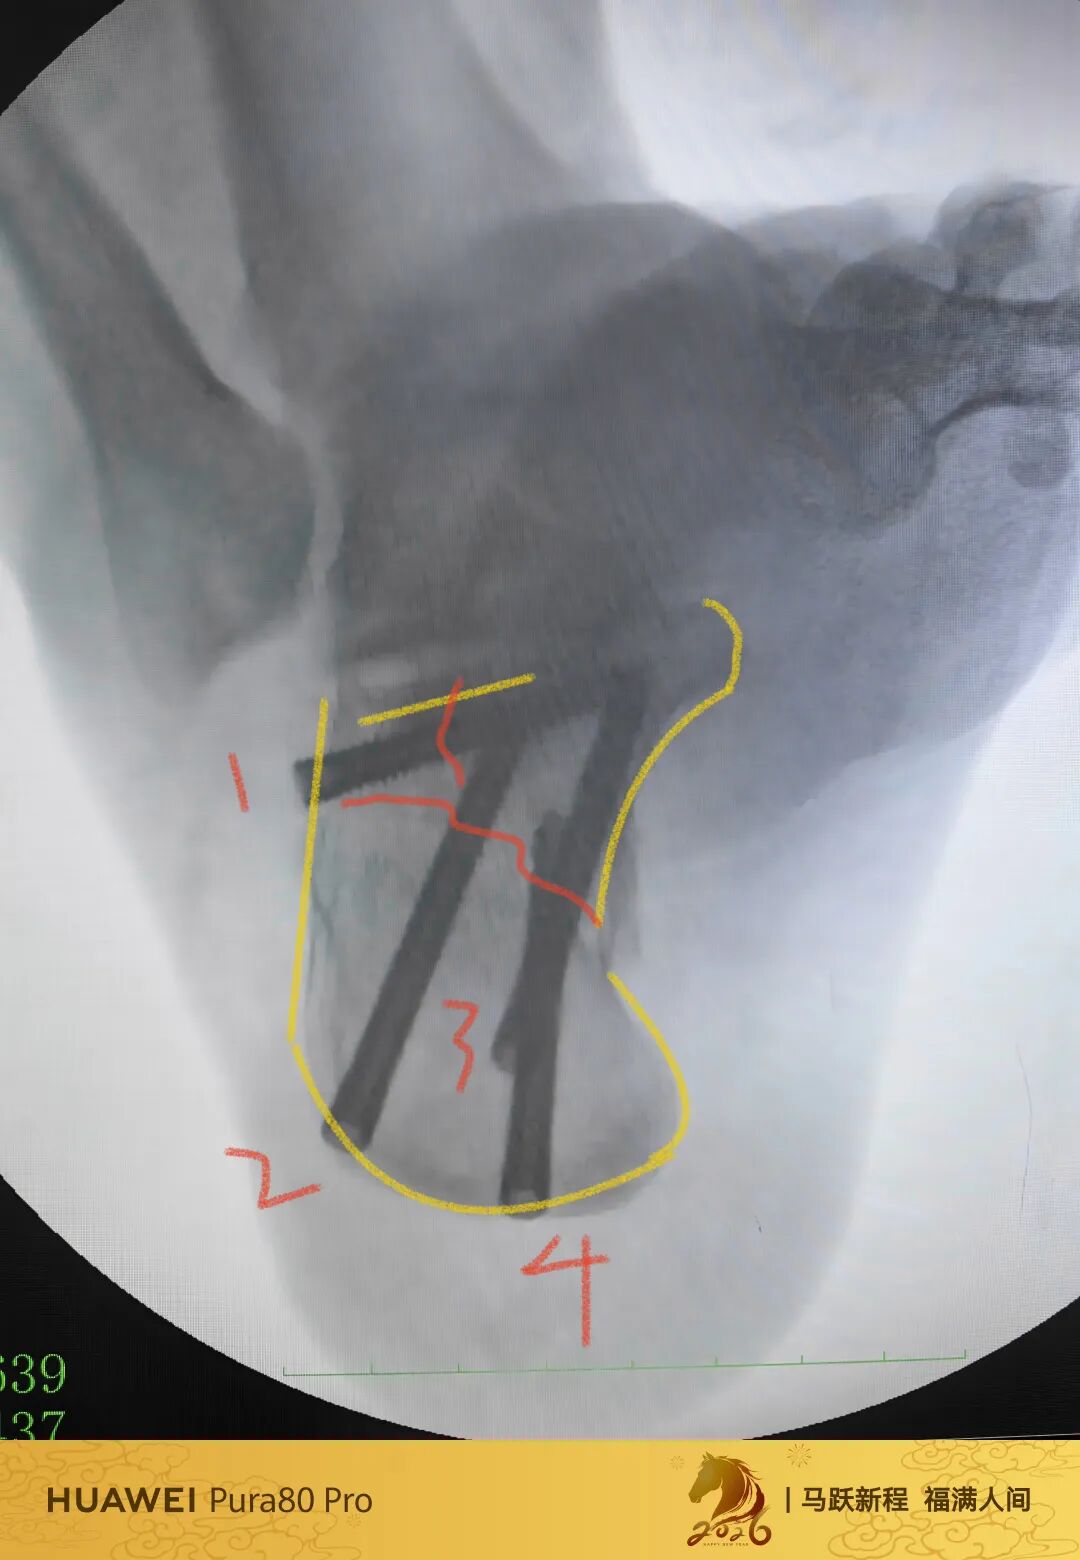

可透视撑开器

高温高压已经消毒10次

低温等离子已经消毒4次

目前来说依旧强硬

强度没问题

高分子材料

质量没得说

第60例跟骨微创了,虽然已经彻底放手,尽量只动嘴,但还是有小问题小瑕疵,无法完全避免。